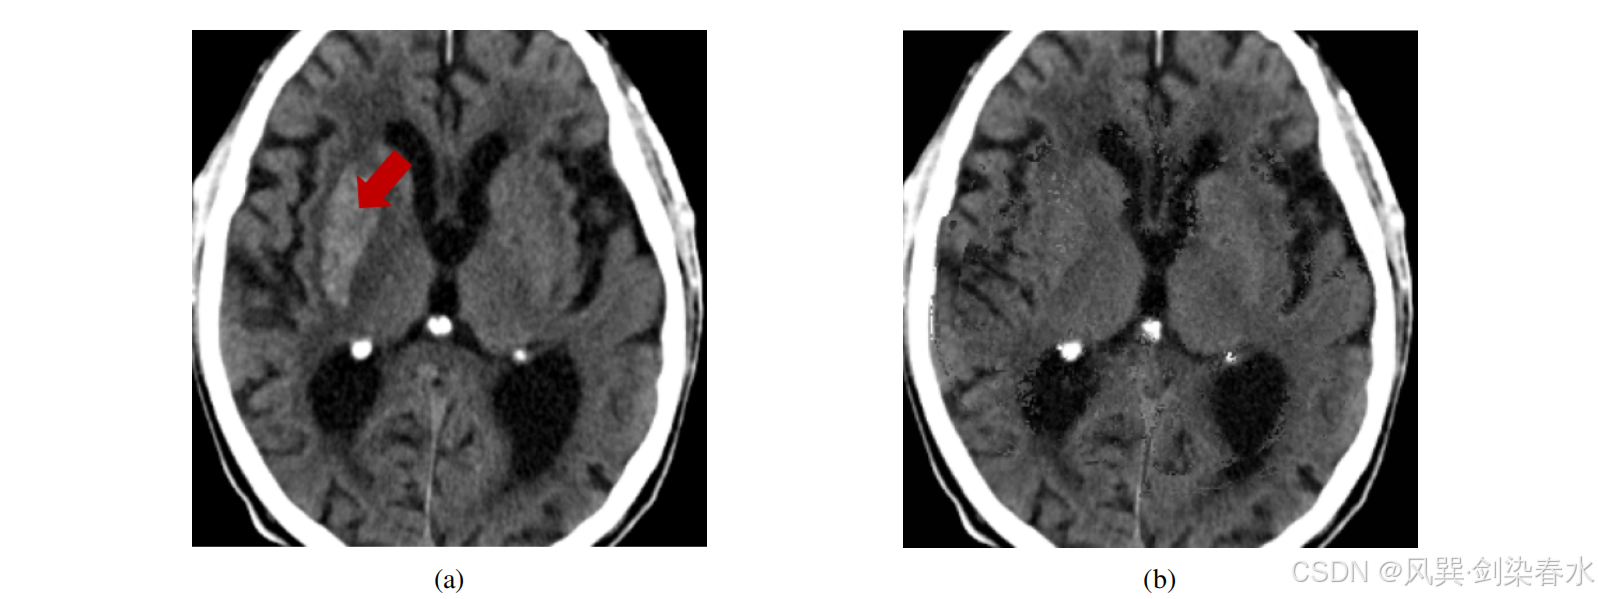

如果只是用 DDPM 计算 x ^ 0 \hat x_0 x^0,然后在采样过程结束时才应用掩模,情况就不会如此。图 3 展示了这种效果,可以看到,仅在采样过程(b)结束时应用掩模生成的正常图像,表现出一些伪影,并且编辑区域和未编辑区域之间缺乏平滑过渡。

Figure 3 | IST-3 的输入图像(a)以及仅在采样过程结束时应用掩码生成的正常图像(b):可以观察到(b)中存在一些伪影,并且编辑部分与未编辑部分之间没有平滑的过渡;